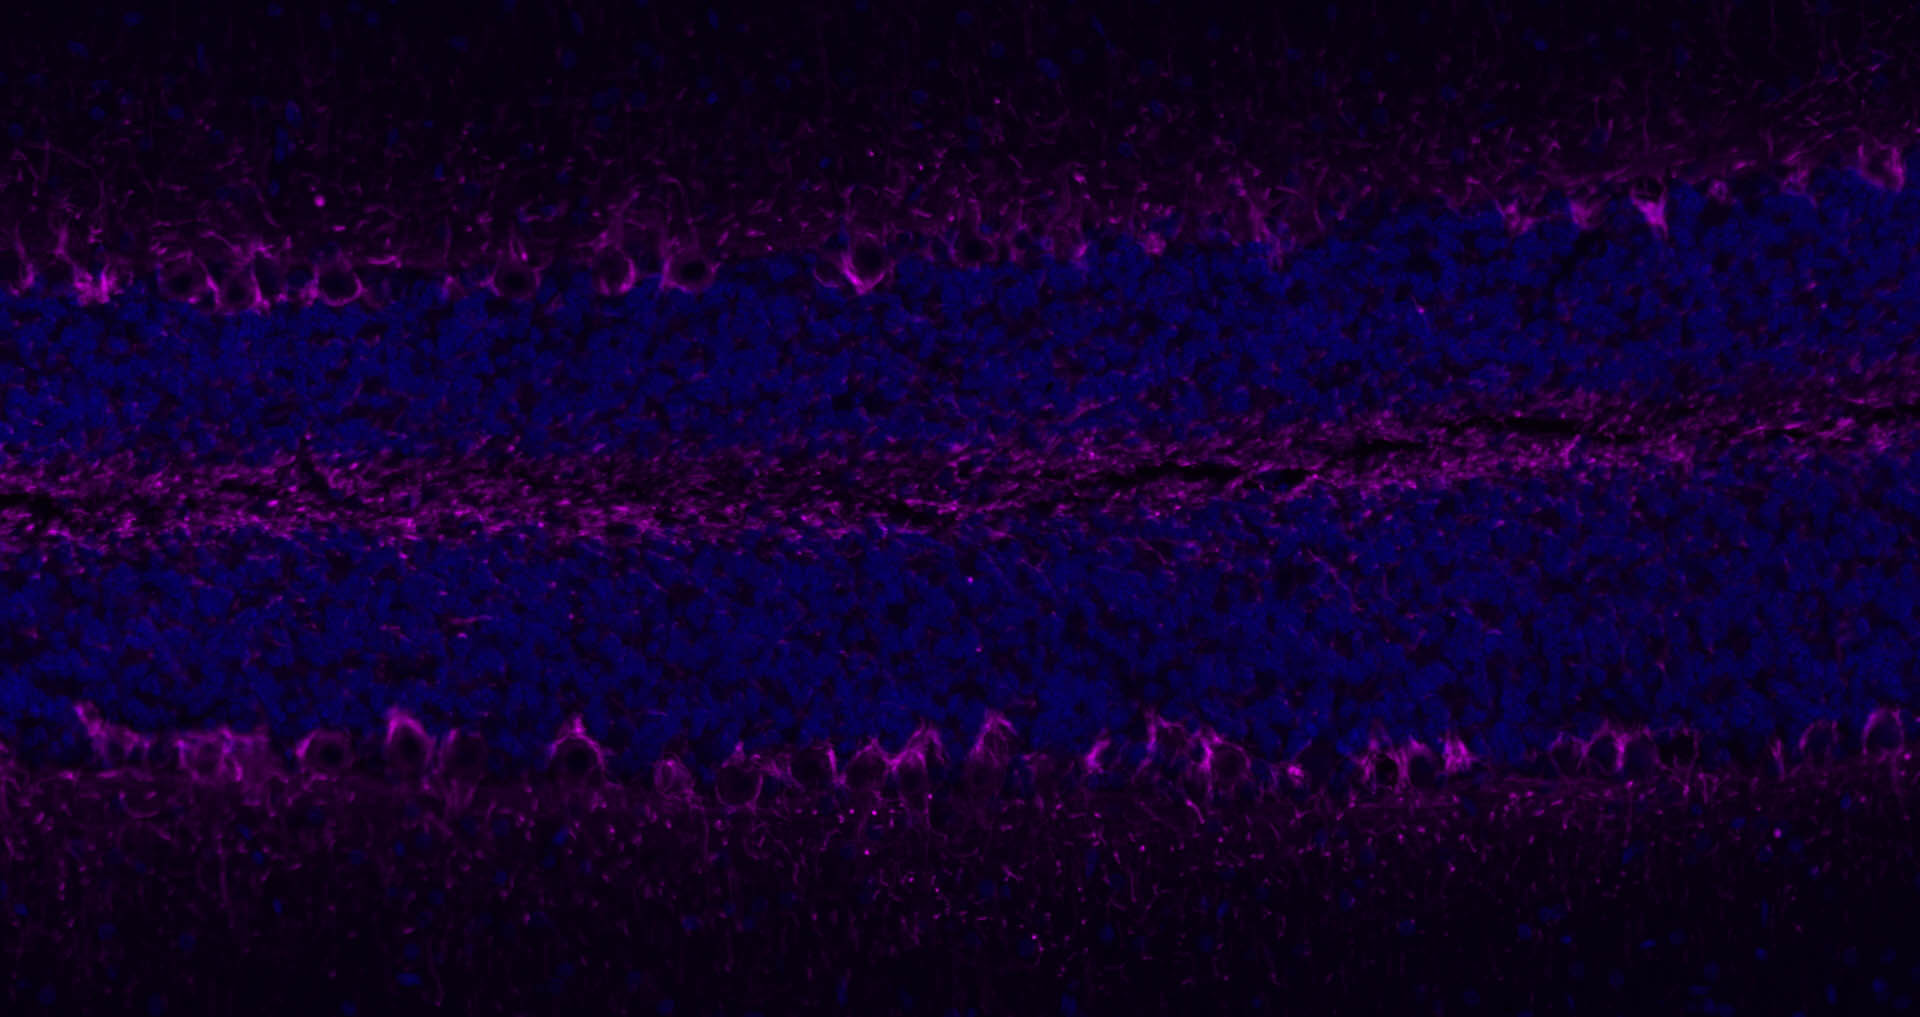

Paraformaldehyde-fixed, paraffin embedded Mouse Cerebellum; Antigen retrieval by boiling in sodium citrate buffer (pH6.0) for 15 min; Antibody incubation with NF-L Polyclonal Antibody, Unconjugated (bs-0707R) at 1:200 overnight at 4°C. Followed by conjugated Goat Anti-Rabbit IgG antibody (Purple, bs-0295D-Cy5), DAPI (blue, C02-04002) was used to stain the cell nuclei.

Paraformaldehyde-fixed, paraffin embedded Rat Cerebellum; Antigen retrieval by boiling in sodium citrate buffer (pH6.0) for 15 min; Antibody incubation with NF-L Polyclonal Antibody, Unconjugated (bs-0707R) at 1:200 overnight at 4°C. Followed by conjugated Goat Anti-Rabbit IgG antibody (Purple, bs-0295D-Cy5), DAPI (blue, C02-04002) was used to stain the cell nuclei.